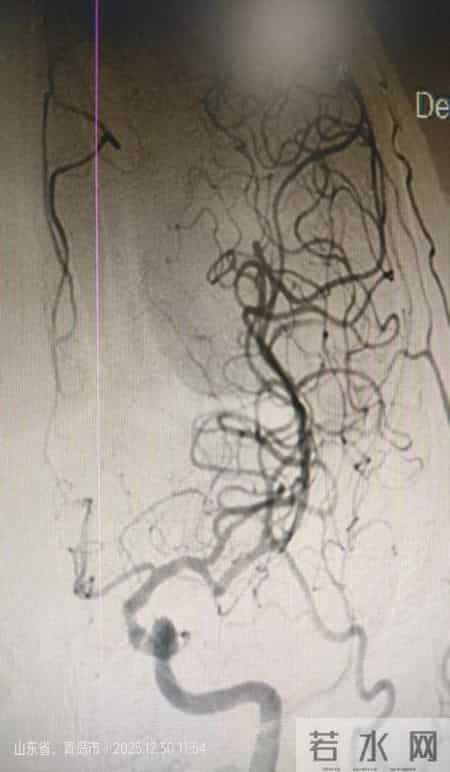

患者B为店子镇昌里村一名82岁的崔大爷,晨起发现右侧肢体无力,伴失语、双眼向左侧凝视,紧急送往平度市第三医院。急诊一键启动卒中绿色通道,经CT、MRI+MRA检查,确诊为一侧大脑中动脉闭塞,情况危急。神经内科介入团队评估后,直接上台取栓。刘文华副主任医师、高学松主治医师配合默契,介入手术室通力合作。术中仅1次抽吸便取出块状红色血栓,术后复查显示闭塞血管完全再通(mTICI 3级),术后即时右侧肢体肌力4+级,出院时患者恢复良好,行走自如。

按照传统医疗模式,上述两例患者若未接受动脉取栓治疗,可能面临长期昏迷,后续梗死后水肿更会让生存希望渺茫。而平度三院神经介入团队,从术前快速评估、制定个性化方案,到术中精准穿刺、取栓复流,全程独立完成,以微创、精准的技术直达血栓“堵点”,快速打通脑部血流生命线,让患者重获新生,重返社会。